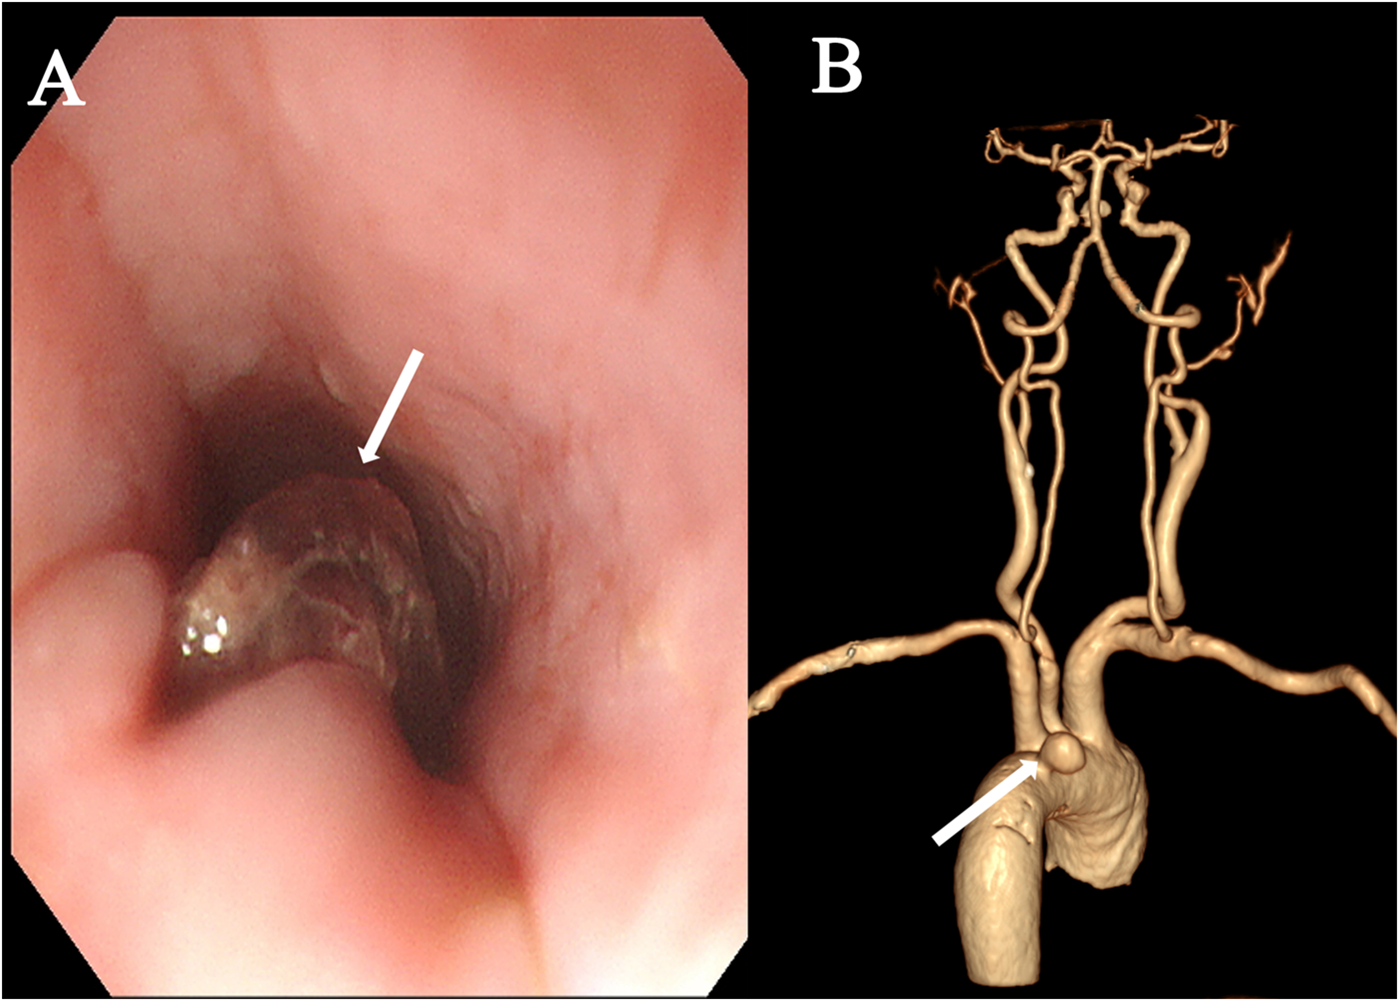

A 74-year-old female was admitted with a 10-day history of chest pain radiating to the back after eating fish, and a 6 h history of hematemesis (approximately 300 ml). An emergency gastroscopy at a local hospital revealed a foreign body (suspected fish bone) 20 cm from the incisors (Figure 1A). Upon transfer to our emergency room, she experienced another episode of massive hematemesis. On admission, she was lethargic with a heart rate of 140 beat per minute, blood pressure of 81/43 mmHg, SpO2 of 75%, hemoglobin of 43 g/L, and lactate of 7.2 mmol/L. Emergency endotracheal intubation was performed. A thoracic aortic computed tomography angiography (CTA) demonstrated a ruptured pseudoaneurysm (Figure 1B). From the patient's viewpoint, the initial hemorrhage was abrupt and terrifying. She valued rapid bleeding control but later felt anxious due to recurrent fever and the possibility of rebleeding. Clear communication about infection control steps and follow-up planning was essential to her sense of safety.

Figure 1

Preoperative examination. (A) Emergency gastroscopy revealing a suspected fish bone foreign body within the esophagus (arrow). (B) Thoracic aortic CTA demonstrated a ruptured pseudoaneurysm (arrow).